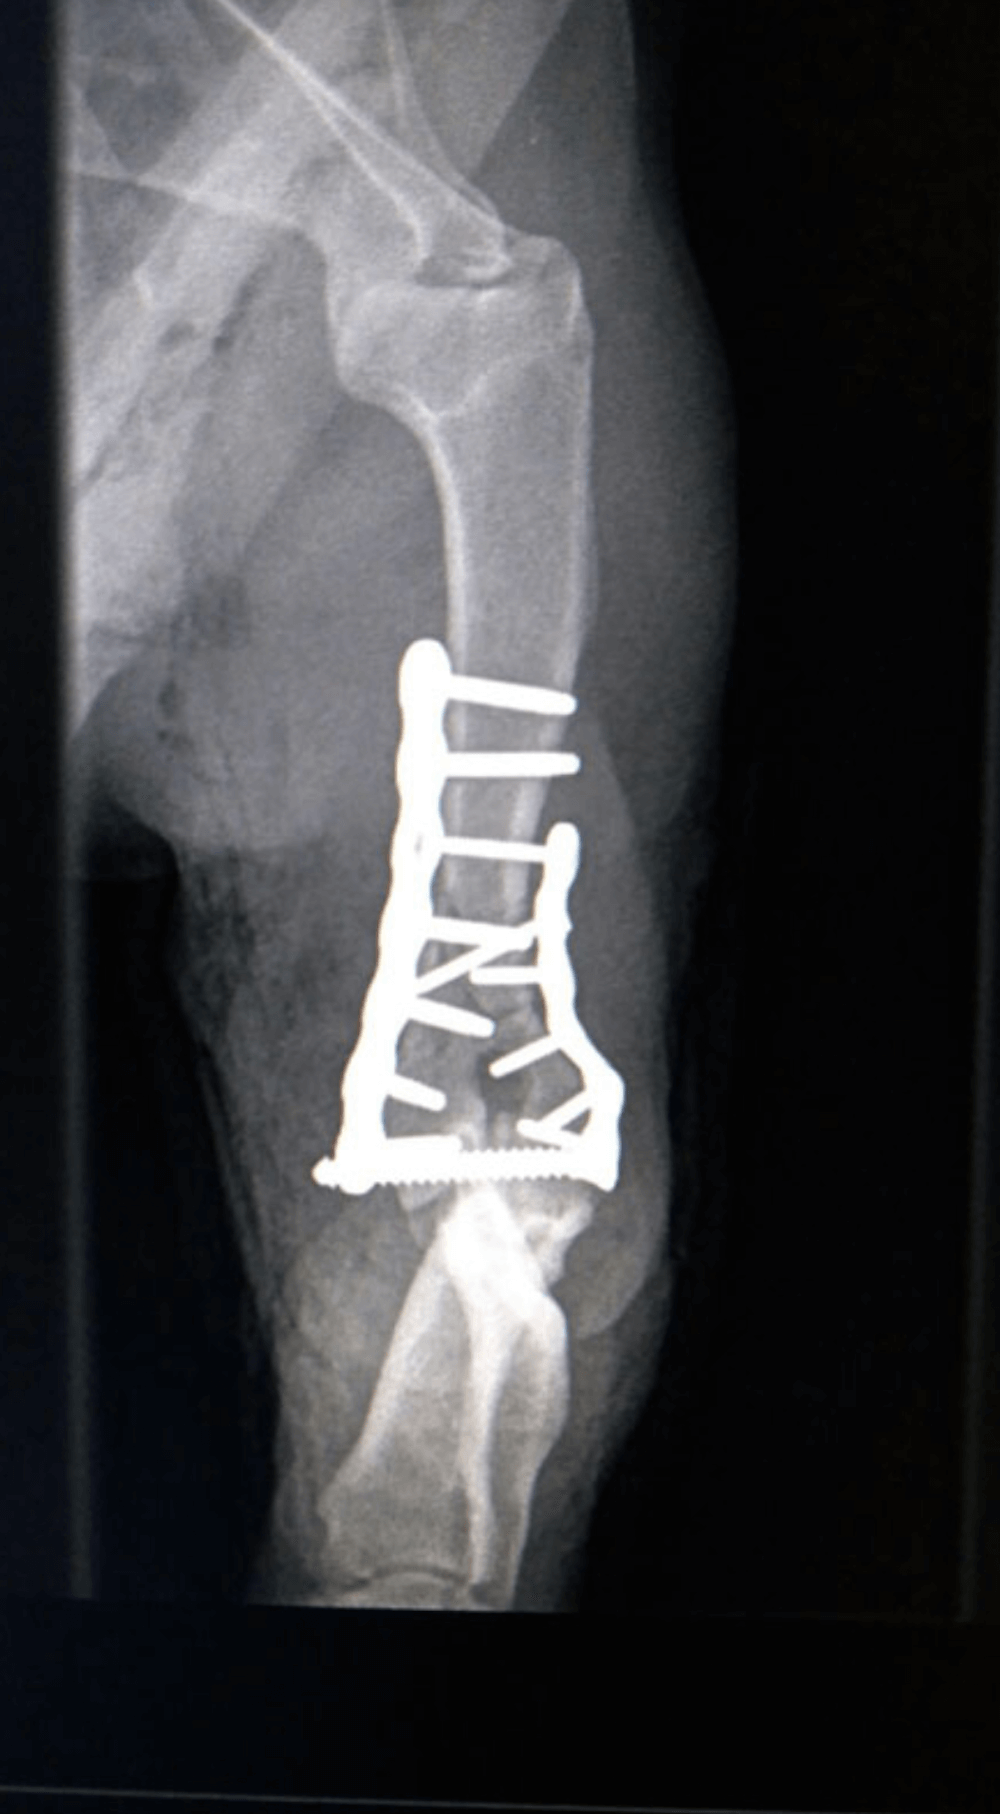

Y Fracture Repair

In a Springer Spaniel.